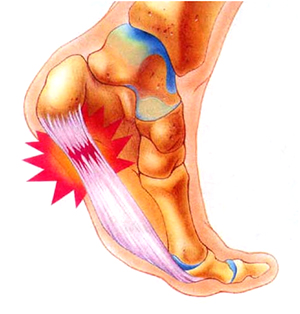

발 뒤꿈치에서부터 발바닥 앞쪽까지의 발바닥 근육을 감싸고 있는 두꺼운 근막이 "족저근막"이라고 합니다. 족저근막이 발바닥의 아치를 유지하고, 걸을 때 스프링처럼 완충 작용을 하여 발을 보호해 주는 기능을 하는데, 이 족저 근막에 반복적인 미세 손상을 입어 염증이 발생한 것을 "족저근막염"이라고 합니다. 대게 40~50대의 여성에게 많이 발생합니다.

대부분 발바닥 중앙 부분부터 통증이 시작되어 발바닥이 걷거나 서 있는 동안에 더 심하게 통증이 느껴지집니다. 아침에 일어나자마자 첫 발을 디딜 때 발바닥에 통증이 심합니다. 움직임에 따라 호전될 수도 있지만 다시 통증이 나타날 수 있습니다. 발바닥 근막염이 생기게 되면 발바닥 부위에 염증과 부종이 생기게 될 수 있으며, 발바닥 힘줄 부근에 압력이 가해지면 민감하게 반응하게 됩니다. 그리고 오래 걷거나 뛰거나 활동할 때 통증이 더 심해질 수 있습니다.